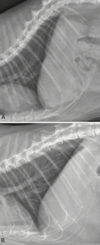

RL or LL (cat)?

LL

RL